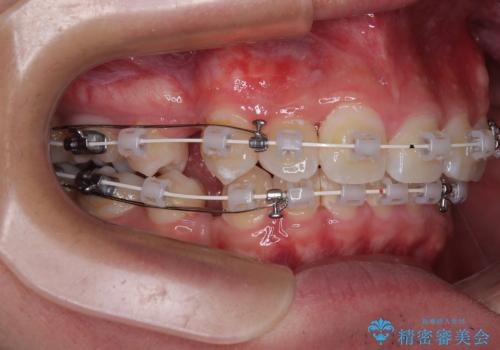

診察の結果、上下の歯が並ぶためのスペースが不足しており、特に上顎右側の側切歯が内側(口蓋側)に転移していたため、正中が大きく右にずれている状態でした。

上下左右の第一小臼歯を抜歯してスペースを確保する計画を立てました。

矯正装置には白いプラスチックブラケットと白いコーティングワイヤーを使用し、見た目にも配慮した治療を行いました。